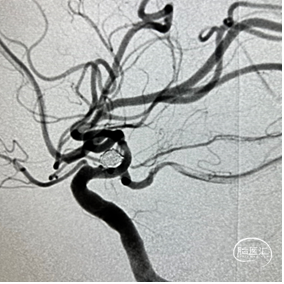

造影显示动脉瘤达到完全致密栓塞,撤出栓塞微导管。

术后工作位及多角度观察,可见Nuva®血流导向密网支架打开良好、充分贴壁,颈内动脉血流正常,动脉瘤腔内可见明显造影剂滞留,分支血管保留良好,手术顺利结束。

【术后右侧颈内动脉正位造影】 【术后右侧颈内动脉侧位造影】

【术后右侧颈内动脉正位造影】 【术后右侧颈内动脉侧位造影】